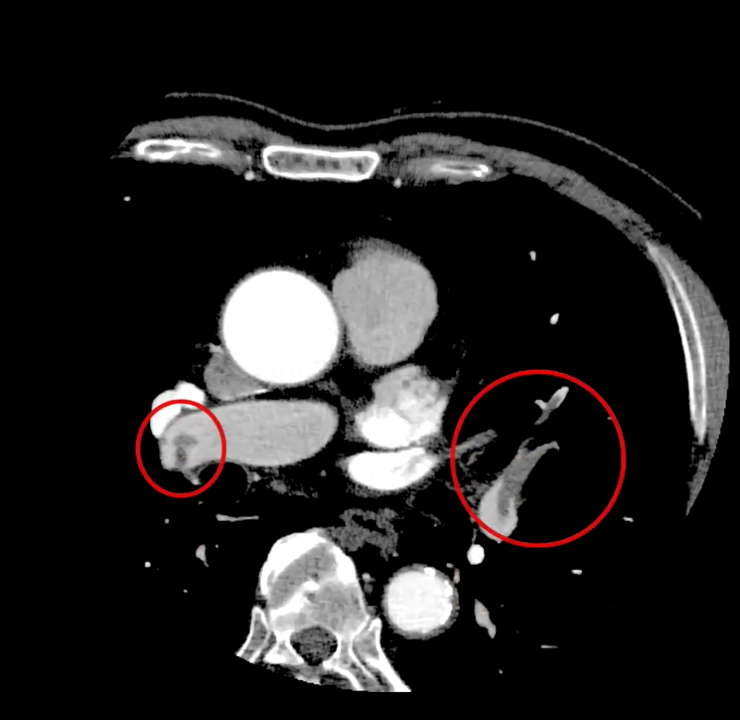

実際の画像ですが、

120kV と比べるとCTは上がっていることがわかります。

当院の臨床画像でも

80kvで撮影した方がDVTの描出が良くなっています。